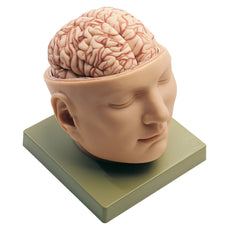

Base of the Head (BS 5/1) · Anatomy models | SOMSO®,

Base of the Head (BS 5/1) · Anatomy models | SOMSO®, SOMSO Situs of the Base of the Skull – GTSimulators.com,

SOMSO Situs of the Base of the Skull – GTSimulators.com, SOMSO Median Section of the Head – GTSimulators.com,

SOMSO Median Section of the Head – GTSimulators.com, Somso Median Section of the Head, Anatomical Model,

Somso Median Section of the Head, Anatomical Model, SOMSO 14-Piece Model of the Human Skull – GTSimulators.com大脳鎌付きの頭部模型です。写真のように細かなパーツにまで分解できます。リアリティのあるものが欲しい方は是非。ちなみに、ヒト頭部骨標本(本物: 下顎、歯牙も全て揃っています)もあります。欲しい方はコメントください。本物で頭蓋底などを勉強したい人にお譲りします。(価格は安くはありませんが、、)

SOMSO 14-Piece Model of the Human Skull – GTSimulators.com大脳鎌付きの頭部模型です。写真のように細かなパーツにまで分解できます。リアリティのあるものが欲しい方は是非。ちなみに、ヒト頭部骨標本(本物: 下顎、歯牙も全て揃っています)もあります。欲しい方はコメントください。本物で頭蓋底などを勉強したい人にお譲りします。(価格は安くはありませんが、、)